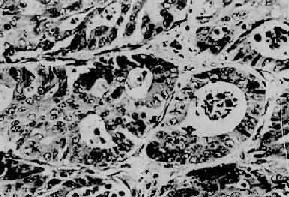

镜下见细胞较小,形态一致,为圆形或多角形,核小而规则。胞浆轻度嗜碱性,有嗜银颗粒,颗粒内含5-羟色胺。细胞形成实体状或索状胞巢,有时可见其中有假菊形团样结构(图10-28)。电镜观察可见细胞浆内有直径100~300nm的球形分泌颗粒,颗粒中有有一电子致密核心,颗粒周边有高电子密度的界膜。常限于粘膜及粘膜下层,少数可达浆膜层。发生在阑尾的类一般恶性度较低,转移率为3%。但发生在其他肠段及其他部位的类,则有约2/3为恶性者,并常转移到肝。

结肠类<a href=癌"/>

图10-28 结肠类